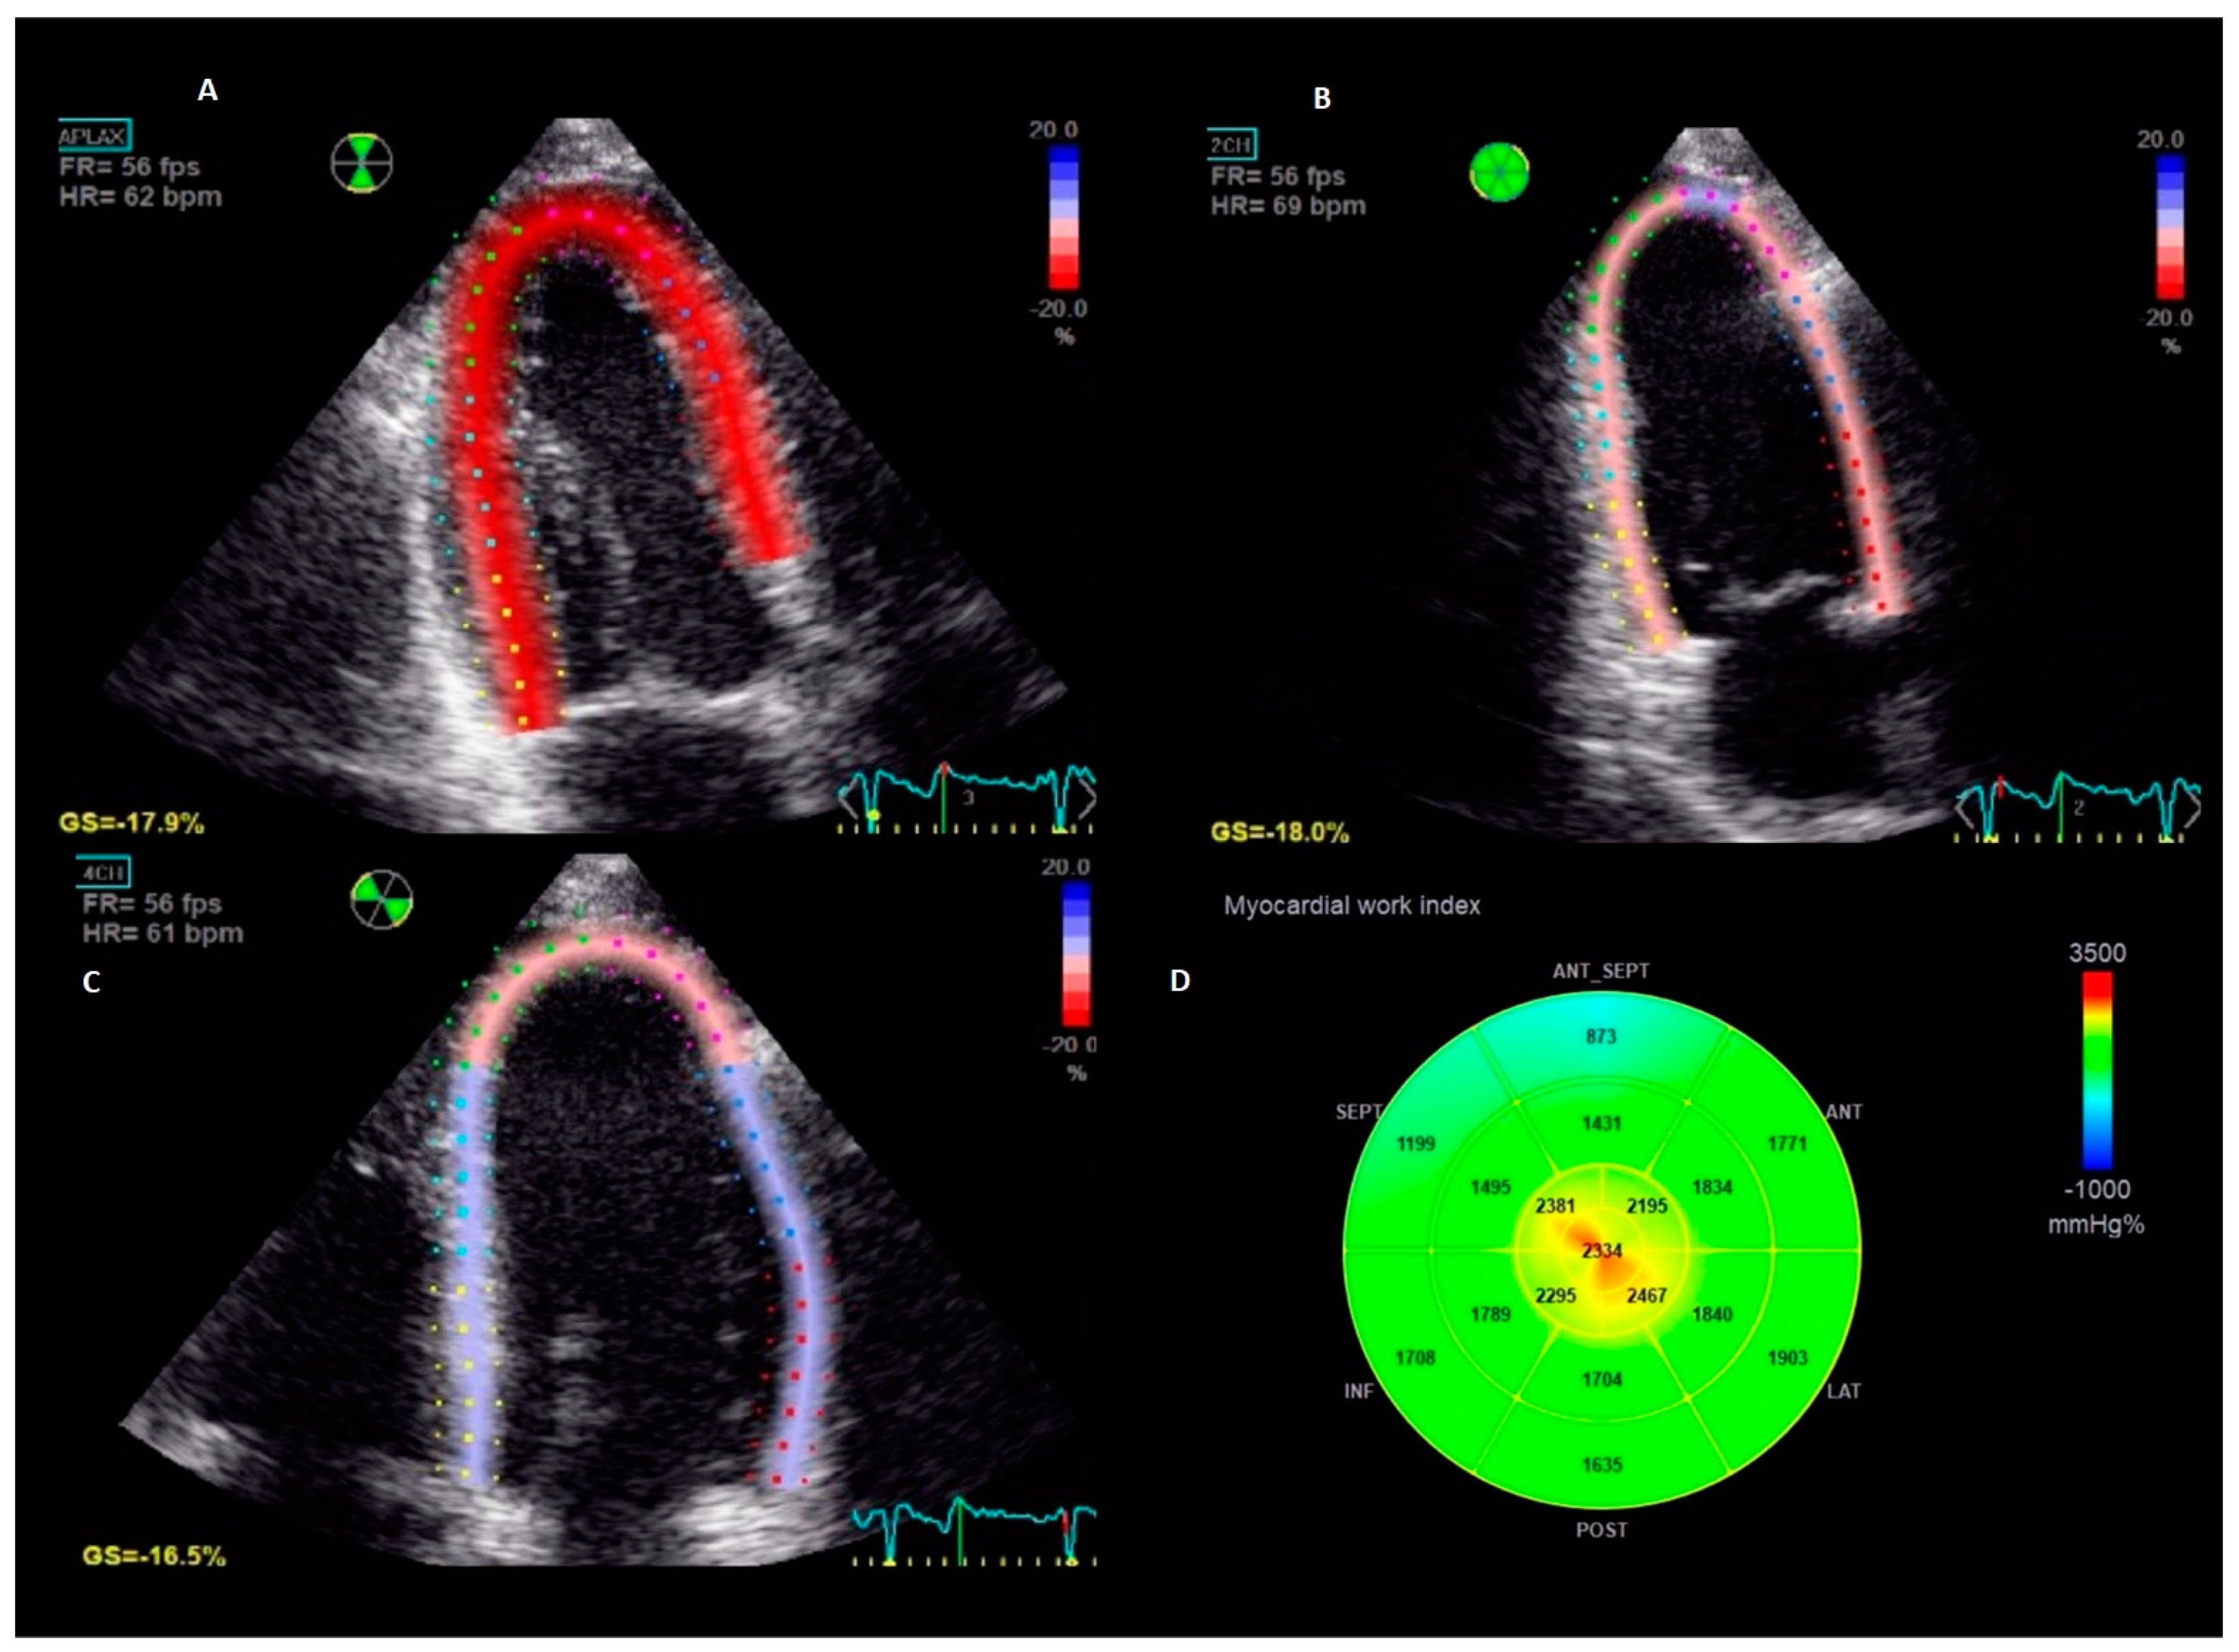

2.5. Myocardial Work Analysis

| Myocardial work | ||||

| Global work index (mmHg%) | 2095 ± 388 | 2126 ± 385 | 2047 ± 389 | 0.031 |

| Global constructive work (mmHg%) | 2333 ± 407 | 2333 ± 407 | 2333 ± 409 | 0.995 |

| Global wasted work (mmHg%) | 75 (49–115) | 73 (49–106) | 77 (50–126) | 0.186 |

| Global work efficiency (%) | 96 (95–97) | 96 (94–97) | 96 (94–97) | 0.138 |